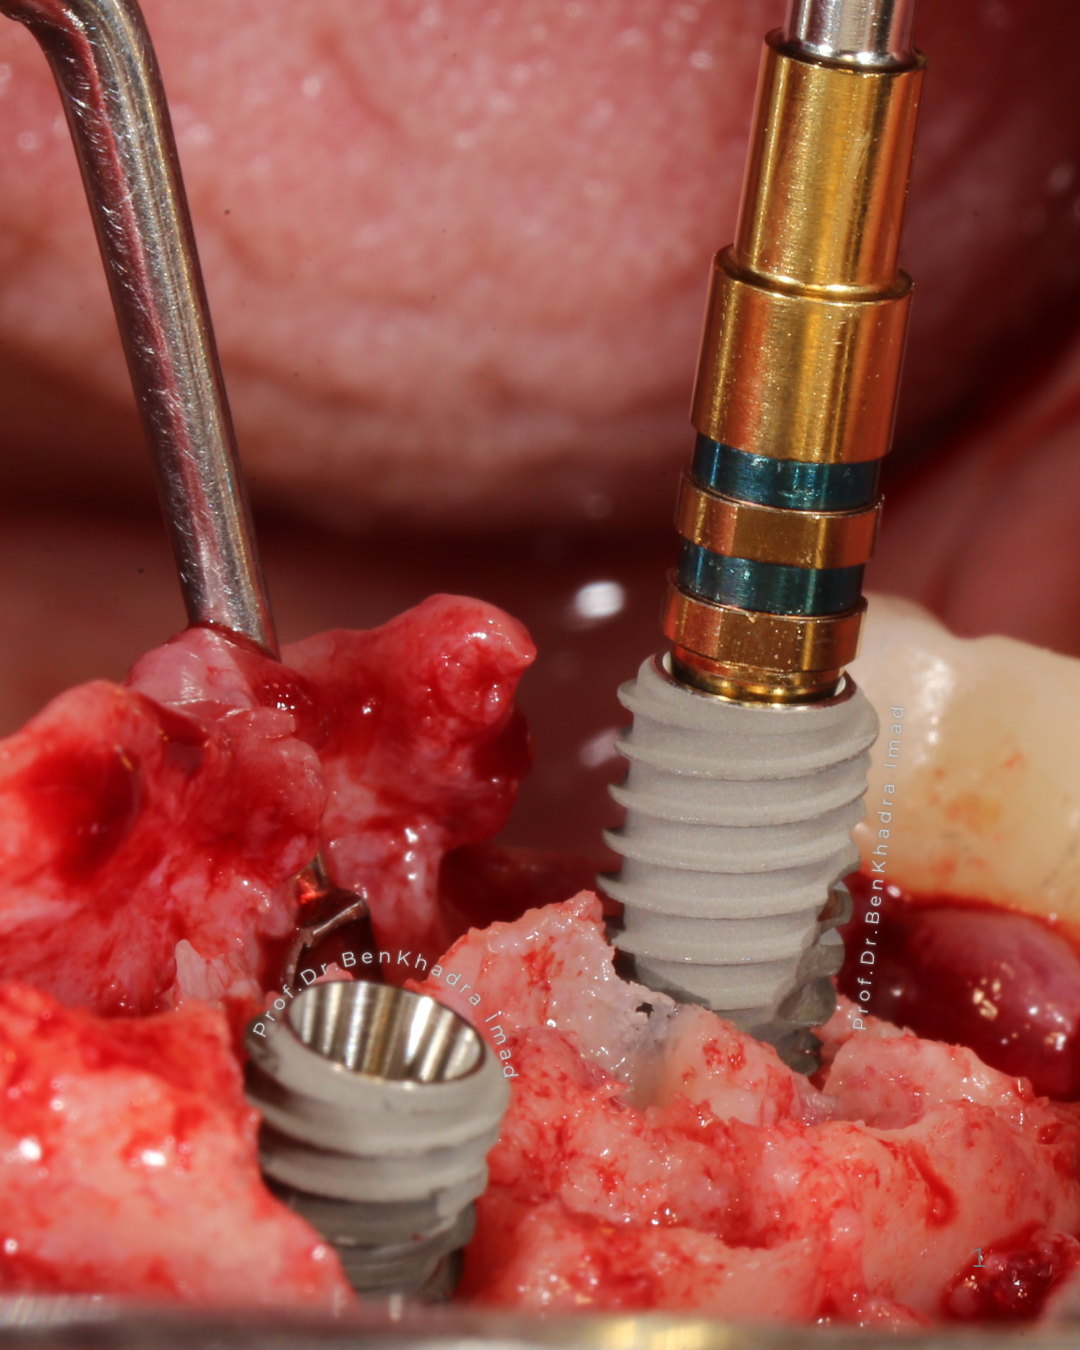

Implant Placement with Precision: Fast and Comfortable Procedure

The dental implant placement procedure is quick, typically taking between 20 to 40 minutes, the surgery is performed under local anesthesia.